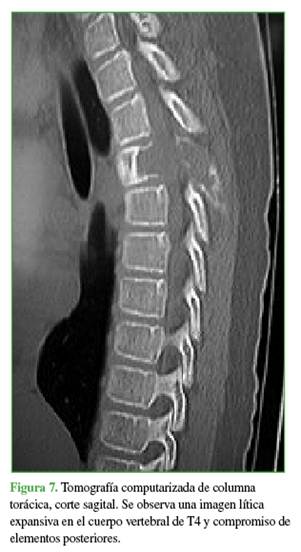

La zona afectada era 3-6, niveles III y IV de la clasificación de Weinstein-Boriani-Biagini.11 En los estudios complementarios, se observaron múltiples quistes tabicados con niveles líquido-líquido, por lo que se descartó un quiste óseo simple, de características expansivas y compresivas, ante este patrón se descartó la posibilidad de un hemangioma vertebral (Figuras 7 y 8). Este caso también se interpretó como una lesión secundaria a un QOA grado 3 de Enneking.13

El plan terapéutico consistió en descomprimir de manera urgente y estabilizar la columna vertebral, en un primer tiempo quirúrgico, y disminuir el riesgo de sangrado mediante una embolización selectiva, con un segundo tiempo de estabilización y artrodesis.